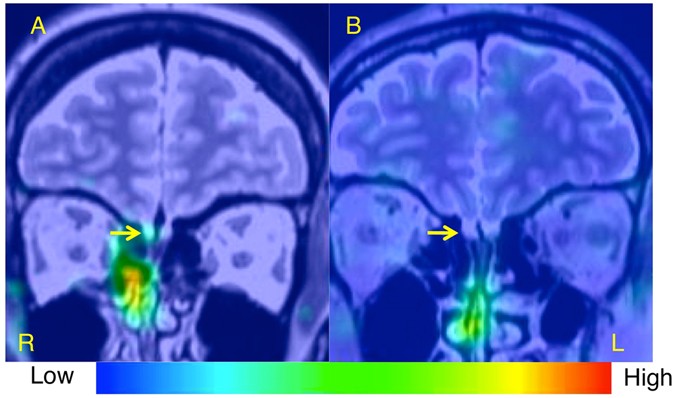

Below, we describe two representative cases of patients with idiopathic olfactory dysfunction. The case with the better prognosis was a 49-year-old female who had relatively high nasal 201Tl migration to the olfactory bulb (11.1%; Fig. 3A). The T&T odor recognition threshold decreased from 4.2 to 0.8 after treatment with the tokishakuyakusan for a month. The case with the worse prognosis was a 40-year-old male who had low nasal 201Tl migration to the olfactory bulb (3.3%; Fig. 3B). The T&T odor recognition threshold increased from 5.0 to 5.8 after treatment with the tokishakuyakusan for 16 months.

Single photon emission computed tomography (SPECT), X-ray computed tomography (CT), and magnetic resonance imaging (MRI) Olfacto-scintigraphy in representative cases with idiopathic olfactory dysfunction. (A) A case of better prognosis was a 49-year-old female who had relatively high nasal 201Tl migration to the olfactory bulb (11.1%). (B) A case of worse prognosis was a 40-year-old male who had low nasal 201Tl migration to the olfactory bulb (3.3%).